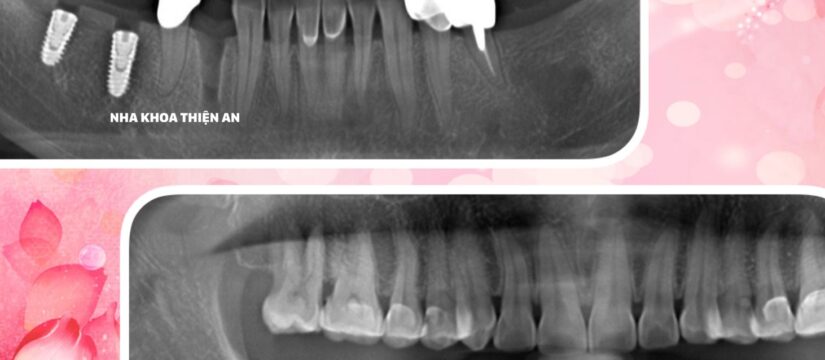

Tiếp tục cấy ghép thêm 1 trụ implant cho chị D sau khi chị trải nghiệm cắm 2 trụ implant tại nha khoa Thiện An BMT – Đăk Lăk nhẹ nhàng, êm ái, với công nghệ Màng PRF được chiết lọc từ chính máu tự thân của chính bệnh nhân để tạo ra các tế bào tiểu cầu, với tác dụng đẩy nhanh sự hồi phục của các mô tổn thương, làm lành các mạch máu, màng PRF có khả năng giúp hồi phục vết thương nhanh hơn, tăng khả năng tích hợp xương của implant

Continue to implant 1 more implant for Ms. D after she experienced 2 implants at Thien An BMT Dental Clinic – Dak Lak gently and smoothly, with PRF Membrane technology extracted from her own autologous blood. patients to create platelet cells, with the effect of hurriedly the recovery of damaged tissues, healing blood vessels, PRF membrane has the ability to help heal wounds faster, increase the ability to integrate bone. of implants